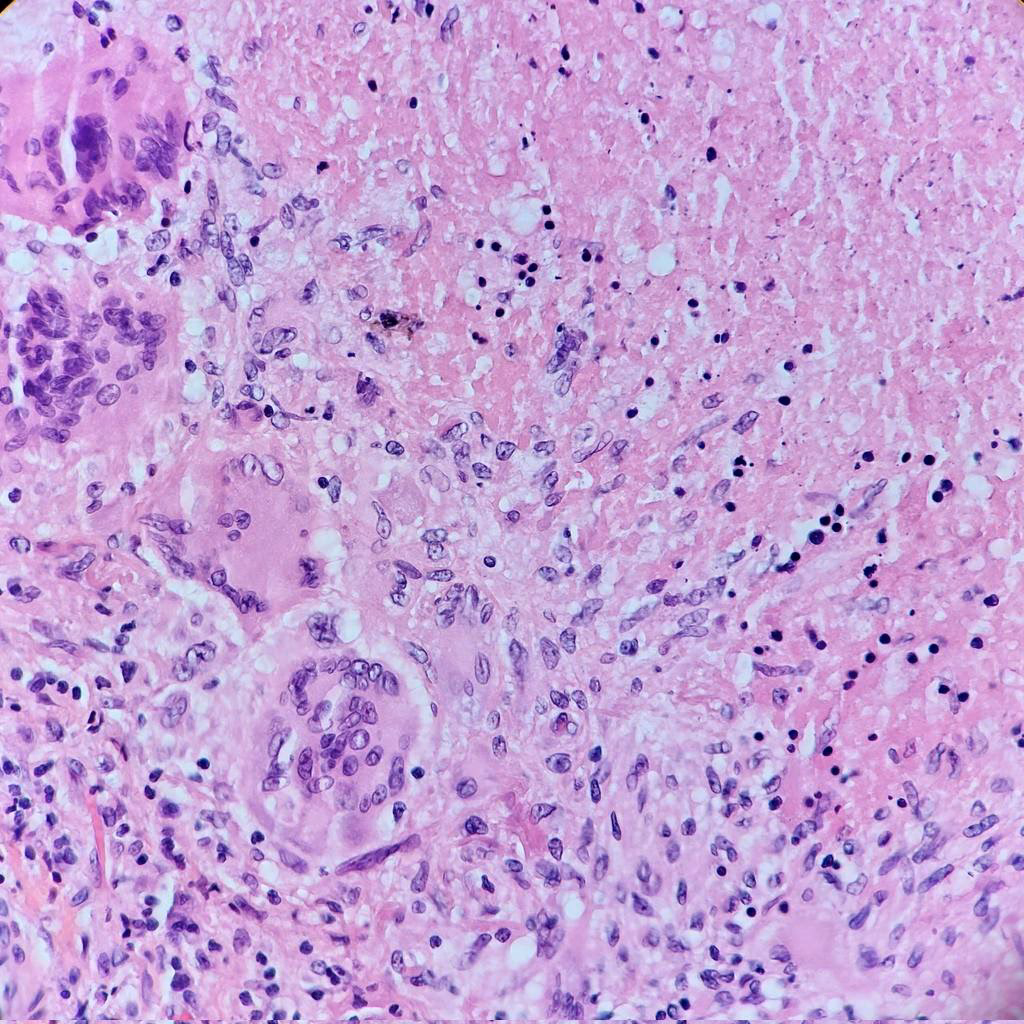

Diagnosekoden A15.0 er en del af Verdenssundhedsorganisationens (WHO) ICD-10-system. Denne specifikke kode bruges af læger og hospitaler til at klassificere "Tuberkulose i lungen, bakteriologisk og histologisk bekræftet". Det betyder, at diagnosen er stillet på baggrund af fund af tuberkulosebakterier i en prøve (f.eks. spyt) eller ved undersøgelse af vævsprøver. Koden dækker over flere relaterede tilstande, herunder:

- Spytprøver (sputumprøver): Den endelige bekræftelse af diagnosen A15.0 kræver påvisning af selve bakterien. Patienten bliver bedt om at hoste en prøve af slim op fra lungerne. Denne prøve undersøges derefter under et mikroskop for at se efter bakterier, og der laves en dyrkning for at få bakterierne til at vokse, hvilket kan tage flere uger. Moderne molekylærbiologiske tests (som PCR) kan give et hurtigere svar.